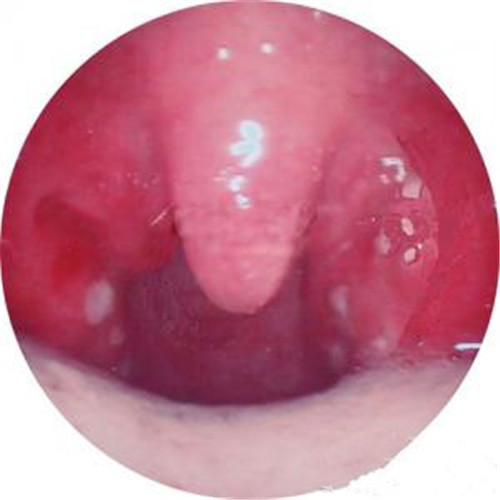

口腔內呼吸道感染

呼吸道感染口腔內部發炎